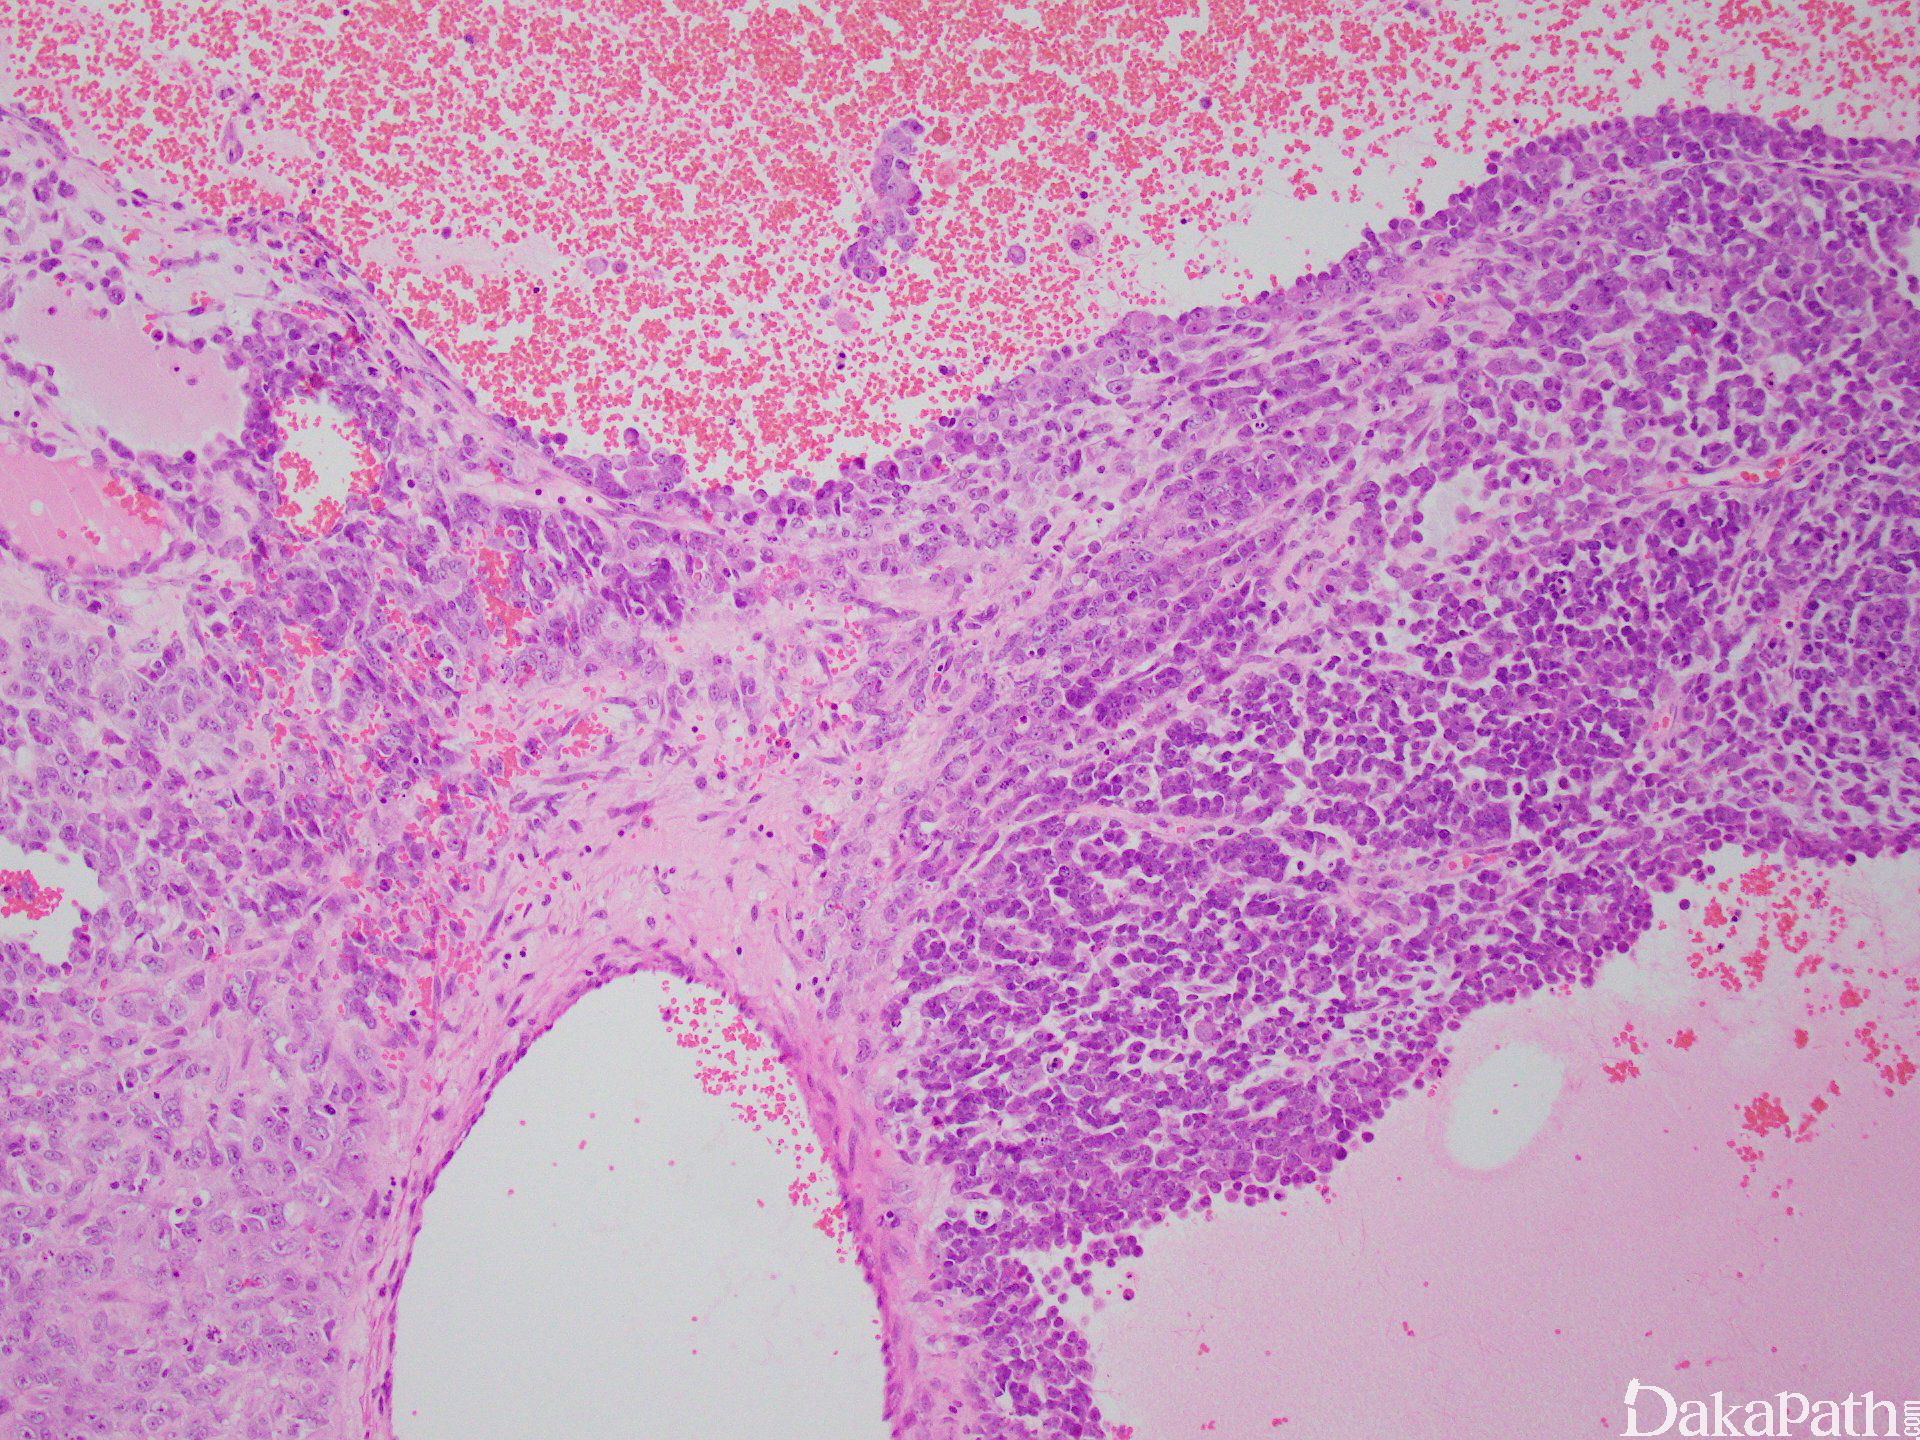

肿瘤细胞呈弥漫片状、密集拥挤的巢状分布,有时呈岛状、小梁状、菊型团样及腺样构型;

细胞小或中等大,圆形至短梭形,胞质少,核深染,染色质似胡椒粉状,核分裂像多见, 坏死常见;